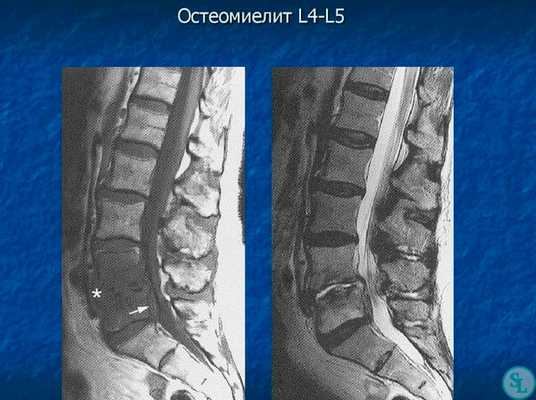

- МРТ позвоночника. Определяется снижение интенсивности сигнала на Т1-взвешенных снимках и его повышение на Т2-взвешенных изображениях, деформация межпозвоночных дисков, структурные изменения тел позвонков. Чувствительность магнитно-резонансной томографии достигает 96%, точность – 94%, поэтому ее считают «золотым стандартом» диагностики.

В диагностике заболеваний позвоночника большей популярностью пользуется магнитно-резонансная томография (или точнее «ядерно-магнитно-резонансная»), более безопасная и чувствительная, чем жесткое рентгеновское излучение. На снимках костные структуры получаются черными, но мягкие ткани, наполненные водой, передают все оттенки серого и белого цветов. Это позволяет обнаруживать мельчайшие объекты (узелковые образования, инфильтрации) и отслеживать динамику развития абсцесса.